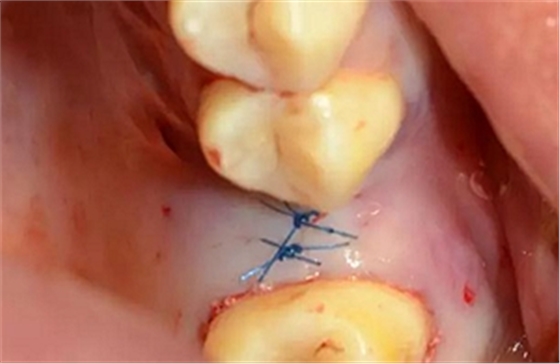

縫合